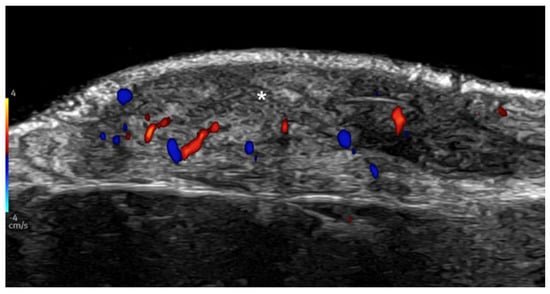

- Cataldo-Cerda, K.; Wortsman, X. Dissecting Cellulitis of the Scalp Early Diagnosed by Color Doppler Ultrasound. Int. J. Trichology 2017, 9, 147–148. [Google Scholar] [CrossRef]